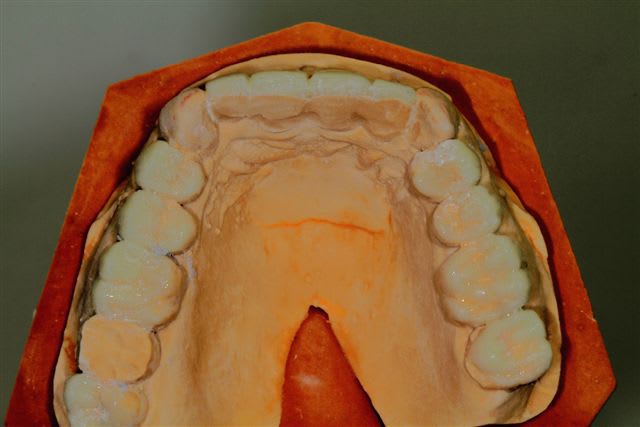

Il semble évident que ceci ne peut être traité que de façon globale, mais la difficulté est de le faire comprendre à la patiente, qui veut seulement un "sourire".

Donc dans un premier temps pano, pour bilan et empreintes pour essayer de lui faire comprendre l'étendue du problème.

premier wax up à minima

Mais autant un wax up ça nous parles, autant la patiente ne déclenche pas, et commence à douter.

La suite, les soins ont commencés le 07/08.

Postérieur bas (16/08)et haut (14/09) en place, essayage des Emax avec "cutback".